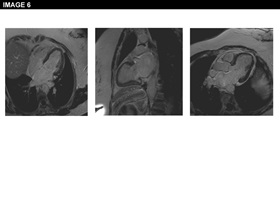

Physical examination is unremarkable. The resting ECG is normal with no ischaemic features (Image 1). She was referred for an ECG exercise stress test. She exercised for 6 min 35 seconds (Bruce protocol), achieved 131% of her heart rate and developed chest pain and breathlessness at peak exercise. Ischemic ST changes were noted which resolved slowly during recovery (Image 2). The patient was referred for cardiac catheterization which showed smooth unobstructed coronary arteries (Image 3). Provocation testing with acetylcholine was performed during angiography when incremental doses of acetylcholine 2mcg, 40mcg, 100mcg were injected in the left coronary system. This resulted in the reproduction of her symptoms, ST depression on the ECG and >75% diffuse epicardial coronary artery spasm of the left coronary artery (Image 4). The diameter of the coronary arteries returned to baseline after intracoronary nitrate administration and both the chest pain and the ECG changes subsided rapidly. Given the diffuse involvement of the distal segments of the coronary artery during the acetylcholine infusion, suggesting the presence of microvascular dysfunction, the patient underwent cardiac magnetic resonance perfusion scanning. Following adenosine stress, which reproduced her usual symptoms, the patient developed subendocardial hypoperfusion of the basal-mid inferior wall & adjacent septum & lateral wall with a circumferential pattern suggestive of microvascular angina (Image 5). On late gadolinium enhancement imaging there was no fibrosis or infarct (Image 6).

A diagnosis of coronary artery spasm and microvascular dysfunction was made and the patient was started on a calcium channel blocker. Both the intensity and frequency of her symptoms improved and the patient returned to her normal every-day activities. While on medical treatment, the patient underwent repeat stress perfusion cardiac magnetic resonance testing. The infusion of adenosine triggered some chest discomfort but no typical chest pain or perfusion defects occurred during the perfusion scan.